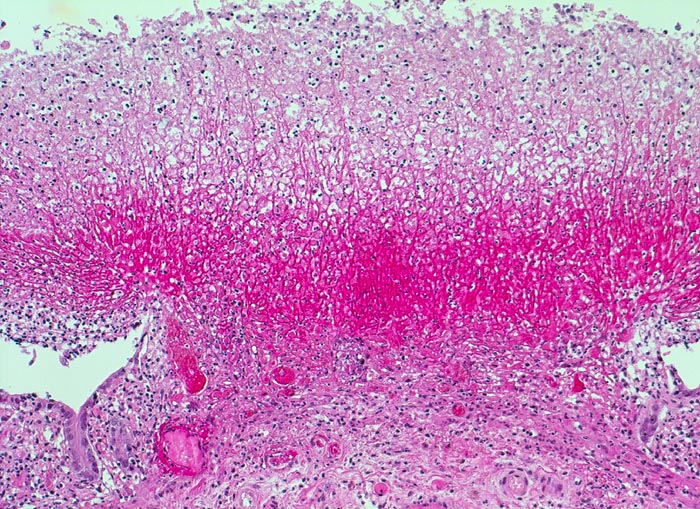

Morphologische Merkmale:

• Herdförmige Schleimhautnekrosen.

• In den Nekrosezonen pilzförmige Pseudomembranen bestehend aus nekrotischem Detritus, Entzündungszellen und Fibrin.

• Zwischen den Pseudomembranen normale Kolonschleimhaut. Das sollte der Kliniker dem Pathologen mitteilen:

In leichten Fällen erscheint das Kolon minimal entzündlich verändert und ödematös. In schwereren Fällen ist die Mukosa bedeckt von locker adhärenten nodulären oder diffusen exsudativen Plaques von 2-5mm Durchmesser, welche konfluieren können. Die morphologische Unterscheidung von einer ischämischen Kolitis kann schwierig sein.